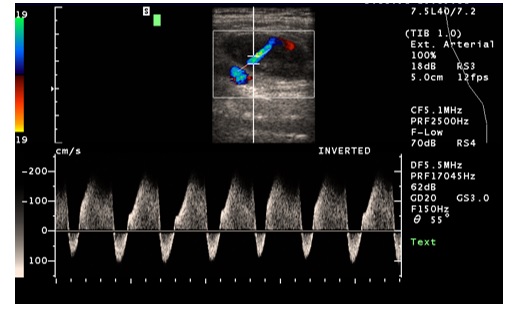

U pacjenta po zabiegu wewnątrznaczyniowym z dostępu przez tętnicę udową w pachwinie stwierdzono obecność krwiaka a osłuchowo obecność szmeru naczyniowego. Wykonano badanie duplex-doppler uzyskując poniższy obraz. Sytuacja przedstawiona na rycinie odpowiada:

Pytanie 110